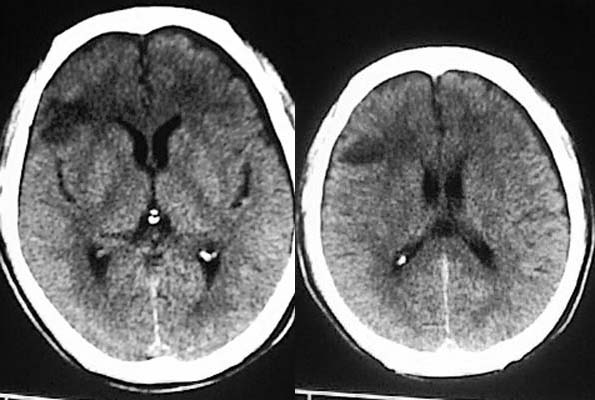

临床予以止血,降颅内压等处理治疗后5日,患者症状缓解,呕吐恶心症状明显减轻,仍然腰背部疼痛乏力。

复查ct:

相信各位都会看这种外伤片,发这个帖子的目的在于请大家讨论右侧额、颞叶交界去的低密度到底是脑挫裂伤还是外伤导致周围血管闭塞引起的脑梗塞,请说出理由!!

相信同行们大部分支持脑挫裂伤,不排除蛛血引起血管痉挛所致脑梗塞,如果要很定那项诊断,还建议增强或mri检查。

左额/顶部硬膜下积液,蛛血,右额叶病灶第一次有高密度影,应该是脑挫裂伤,外伤性脑梗塞应该在第一次照片上就出现.